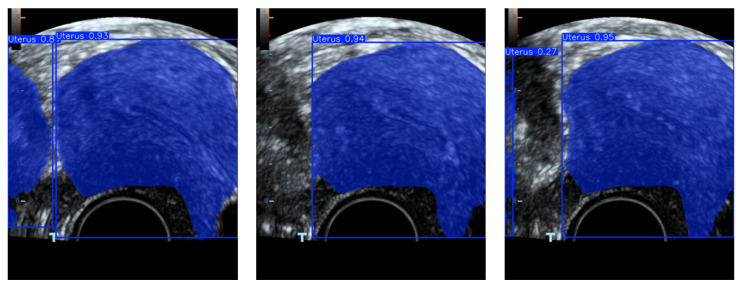

准确识别子宫内膜区域是早期发现子宫内膜病变的关键。然而,目前的检测模型在处理子宫内膜成像数据时仍然面临两大挑战:(1)在复杂和嘈杂的环境中,识别精度仍然有限,部分原因是图像中颜色信息的利用不足;(2)传统的基于二维pca (2DPCA-based)的特征选择方法在捕获和表达子宫内膜区域关键特征方面能力有限。为了解决这些问题,本文提出了一种新的算法,称为特征级图像融合和改进的群体智能优化算法(FLFSI),该算法将学习引导的二进制粒子群优化(BPSO)策略与图像特征选择和重建框架相结合,以增强临床超声图像中子宫内膜区域的检测。具体而言,FLFSI有助于提高特征选择精度和图像重建质量,从而提高区域识别任务的整体性能。首先,我们通过结合结构和颜色信息的特征工程技术增强子宫内膜图像表征,从而提高重建质量并强调关键区域特征。其次,将BPSO算法引入特征选择阶段,提高了特征选择的准确性和全局搜索能力,同时有效降低了冗余特征的影响。在此基础上,对BPSO设计进行了改进,提高了算法的收敛速度和优化效率。本文提出的FLFSI算法可以集成到主流的检测模型中,如YOLO11和YOLOv12。当应用于YOLO11时,FLFSI达到96.6%的Box mAP和87.8%的Mask mAP。利用YOLOv12,进一步将Mask mAP提高到88.8%,表现出优异的跨模型适应性和鲁棒性检测性能。大量的实验结果验证了FLFSI在增强子宫内膜区域检测用于临床超声图像分析方面的有效性和广泛适用性。

Accurate identification of the endometrial region is critical for the early detection of endometrial lesions. However, current detection models still face two major challenges when processing endometrial imaging data: (1) In complex and noisy environments, recognition accuracy remains limited, partly due to the insufficient exploitation of color information within the images; (2) Traditional Two-dimensional PCA-based (2DPCA-based) feature selection methods have limited capacity to capture and represent key characteristics of the endometrial region. To address these challenges, this paper proposes a novel algorithm named Feature-Level Image Fusion and Improved Swarm Intelligence Optimization Algorithm (FLFSI), which integrates a learning guided binary particle swarm optimization (BPSO) strategy with an image feature selection and reconstruction framework to enhance the detection of endometrial regions in clinical ultrasound images. Specifically, FLFSI contributes to improving feature selection accuracy and image reconstruction quality, thereby enhancing the overall performance of region recognition tasks. First, we enhance endometrial image representation by incorporating feature engineering techniques that combine structural and color information, thereby improving reconstruction quality and emphasizing critical regional features. Second, the BPSO algorithm is introduced into the feature selection stage, improving the accuracy of feature selection and its global search ability while effectively reducing the impact of redundant features. Furthermore, we refined the BPSO design to accelerate convergence and enhance optimization efficiency during the selection process. The proposed FLFSI algorithm can be integrated into mainstream detection models such as YOLO11 and YOLOv12. When applied to YOLO11, FLFSI achieves 96.6% Box mAP and 87.8% Mask mAP. With YOLOv12, it further improves the Mask mAP to 88.8%, demonstrating excellent cross-model adaptability and robust detection performance. Extensive experimental results validate the effectiveness and broad applicability of FLFSI in enhancing endometrial region detection for clinical ultrasound image analysis.